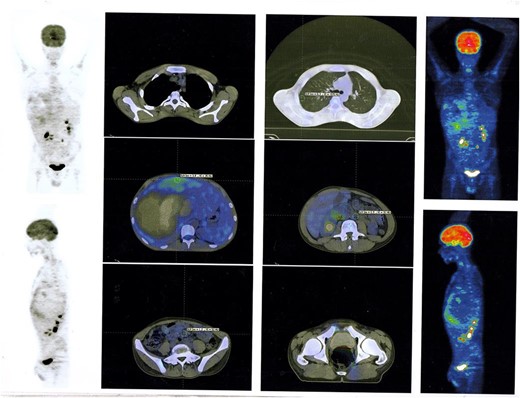

In succession, the Positron Emission Tomography (PET) Scan Multi Slice revealed a peripherally slightly metabolically active hepatic mass (205 × 134 × 208 mm) with a wide necrotic component and inactive mesenteric, retroperitoneal, and pulmonary nodes (Fig. 2).

PET Scan Multi Slice revealed a peripherally slightly metabolically active hepatic mass (205 × 134 × 208 mm) with a wide necrotic component and inactive mesenteric, retroperitoneal, and pulmonary nodes.